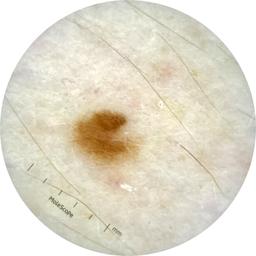

ISIC_9785574

Information

2003 x 2003

Attribute to

MEL-SELF Trial, https://www.sydney.edu.au/medicine-health/our-research/research-centres/melself-project.html

License

Clinical

Field Value

acquisition_day 148

age_approx 45

anatom_site_1 Head and neck

anatom_site_general head/neck

concomitant_biopsy False

diagnosis_1 Benign

diagnosis_confirm_type single image expert consensus

family_hx_mm True

image_manipulation instrument only

image_type dermoscopic

lesion_id IL_0236417

patient_id IP_8456088

personal_hx_mm True

sex female